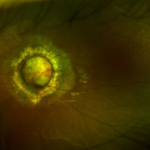

What Does It Look Like?

โข Multiple small, round, fluid-filled areas in the epithelium

โข Uniformly arranged in a honeycomb-like pattern

โข Best viewed with slit-lamp biomicroscopy or anterior segment OCT